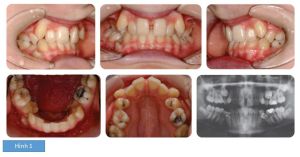

Kết quả thu được tại hình 2.